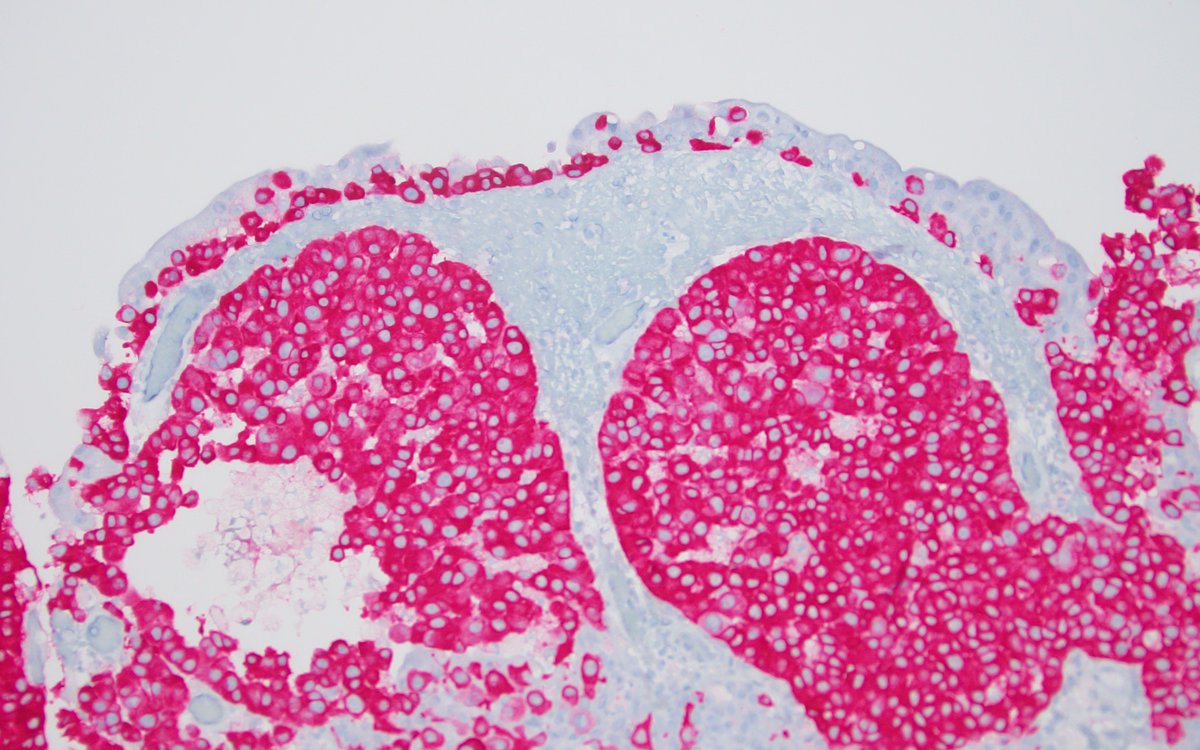

Lipid-rich urothelial carcinoma ✔️frequently associated with conventional urothelial carcinoma ✔️ lipid nature of the vacuolar content has been confirmed by EM ✔️ poor prognosis ✔️ + CK7, CK20 (photo), 34betaE12 #gupath #pathology #uropathology